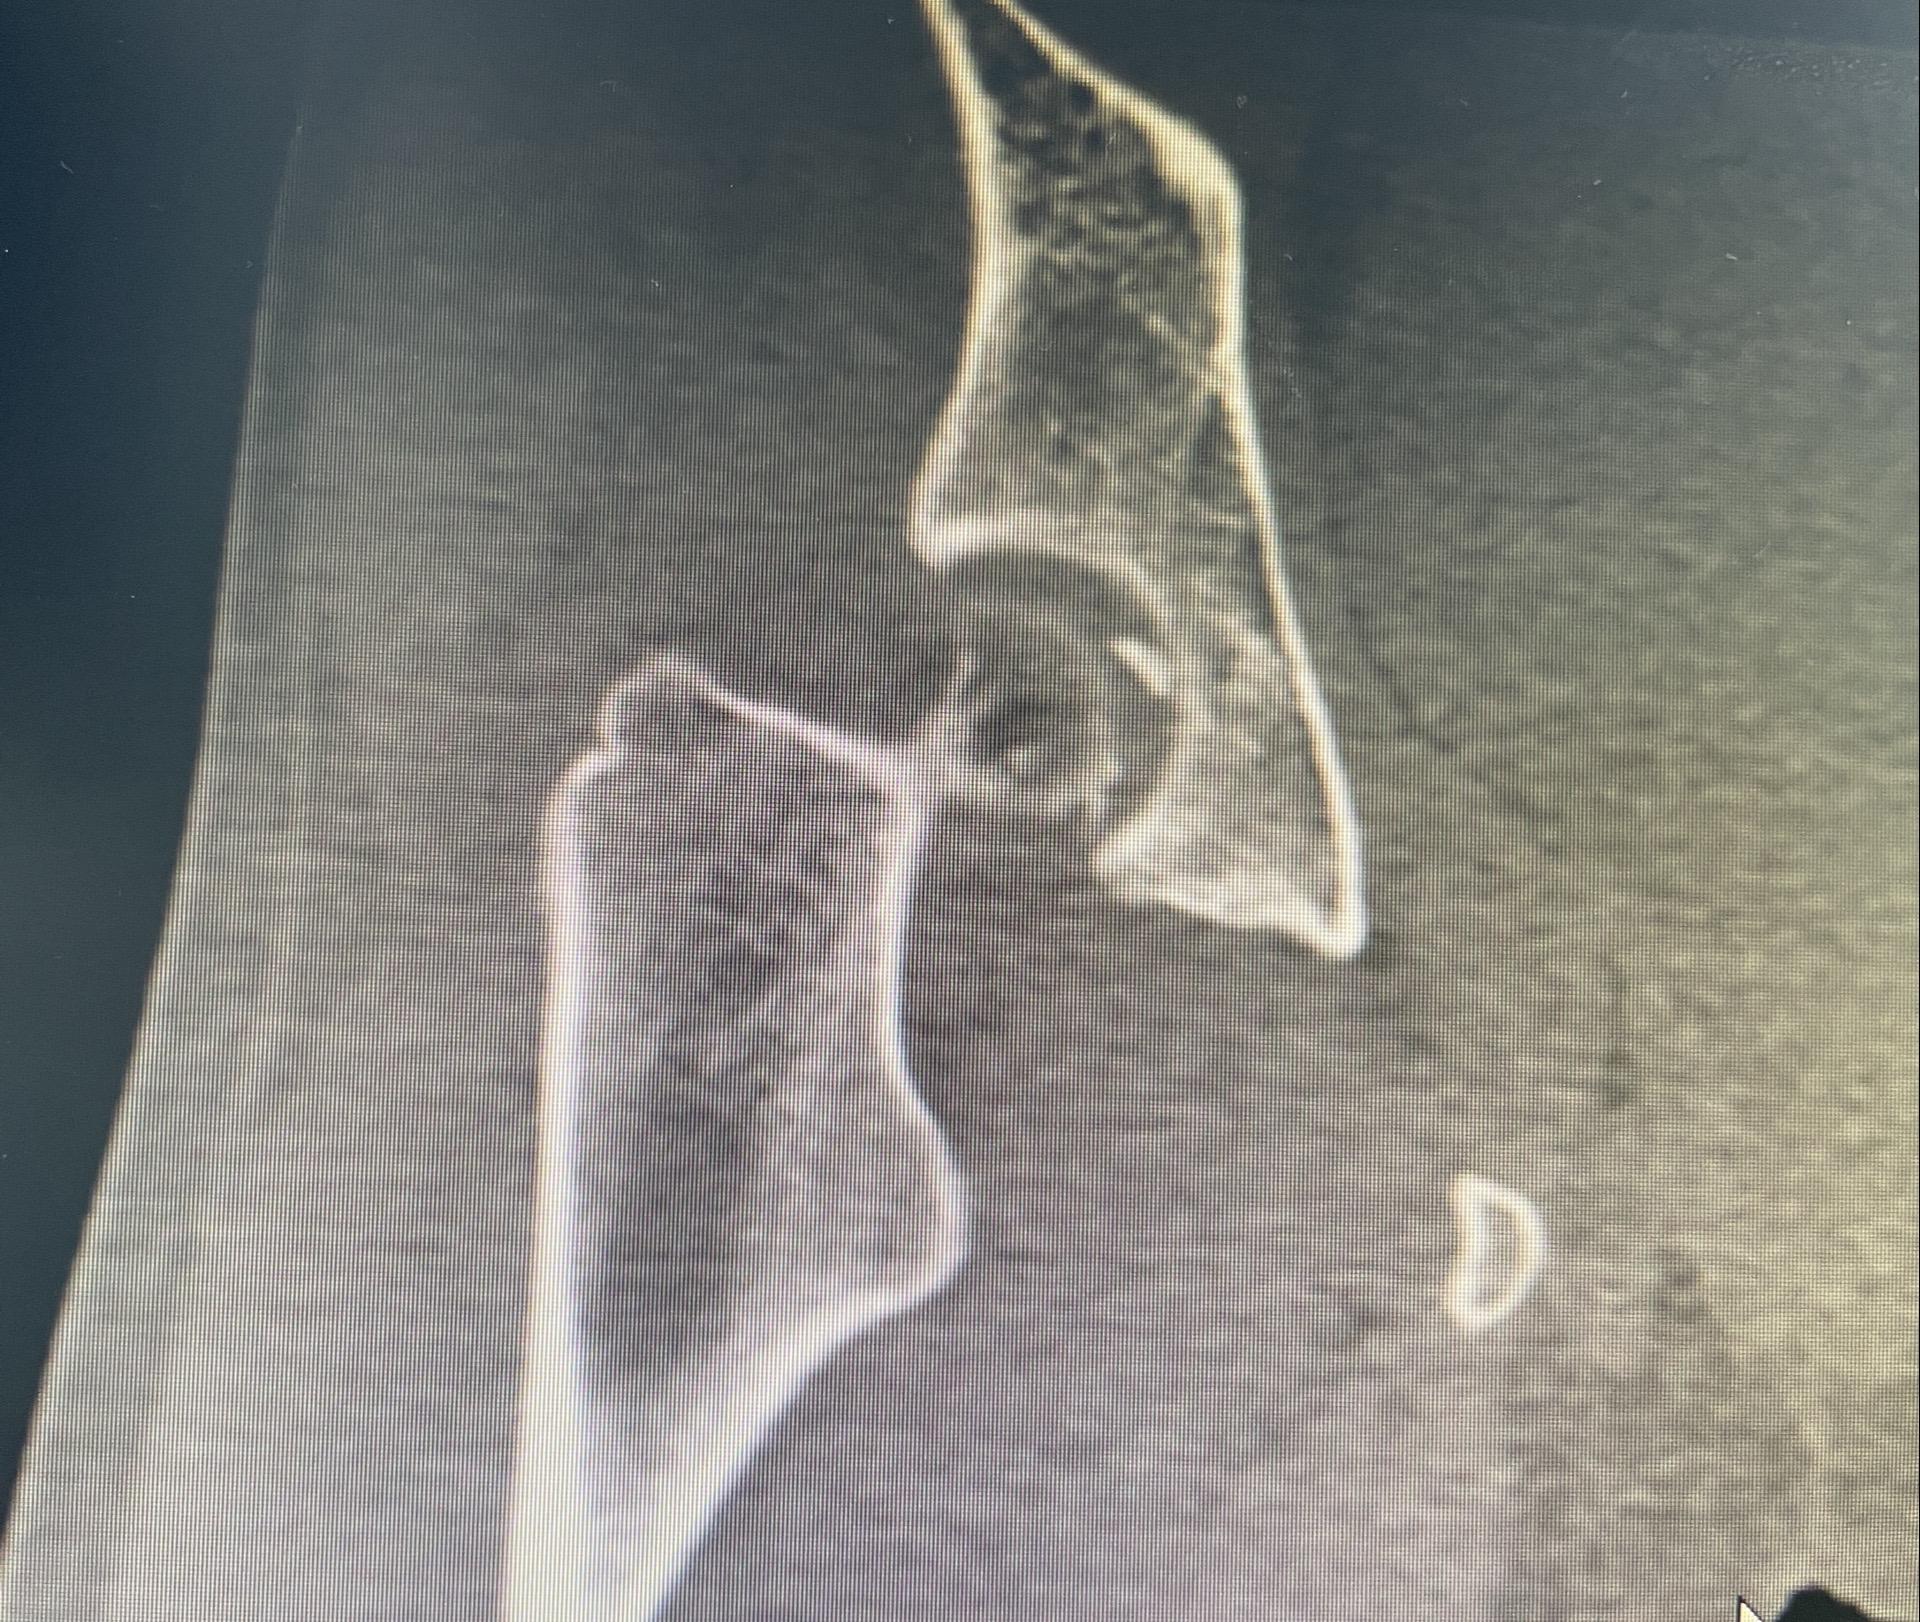

髋关节镜下游离体取出。髋关节脱位,股骨头圆韧带撕脱性骨折,髋关节镜下取出游离骨块。